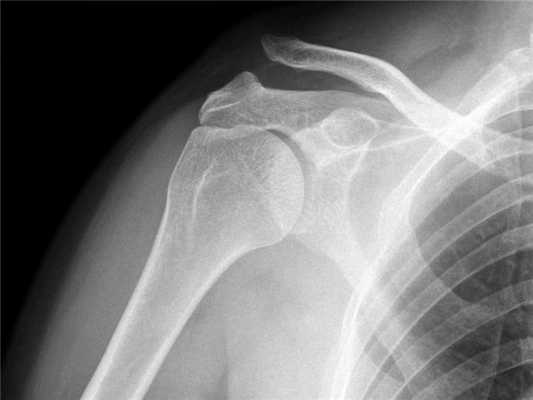

Для подстверждения диагноза выполняется рентгенография плечевого сустава. На рентгенограмме четко видно, если произошел вывих акромиального конца ключицы.

Диагноз вывиха акромиального конца ключицы

Диагноз вывиха акромиального конца ключицы иногда очень прост и все очевидно при осмотре, а иногда приходится решать целую головоломку. Наиболее оптимальным и распространенным способом диагностики является рентгенография. Стоит сказать, что, как не бывает одинаковых людей, так и не бывает одинаковых ключиц. Чаще всего причиной ложного диагноза индивидуальные особенности акромиально-ключичного сустава.

Поэтому целесообразно выполнять рентгенограмму не одного плеча, а двух сразу - что позволит оценить нормальное строение противоположной ключицы.

Практически во всех случаях определить получение вывиха ключицы оказывается достаточно легко, с учетом проявляемых клинических признаков. Из дополнительных методов исследования больному может быть назначено проведение рентгеновского исследования. Для правильного установления диагноза, целесообразно выполнять рентгенограмму здорового и больного плеча на одной пленке.